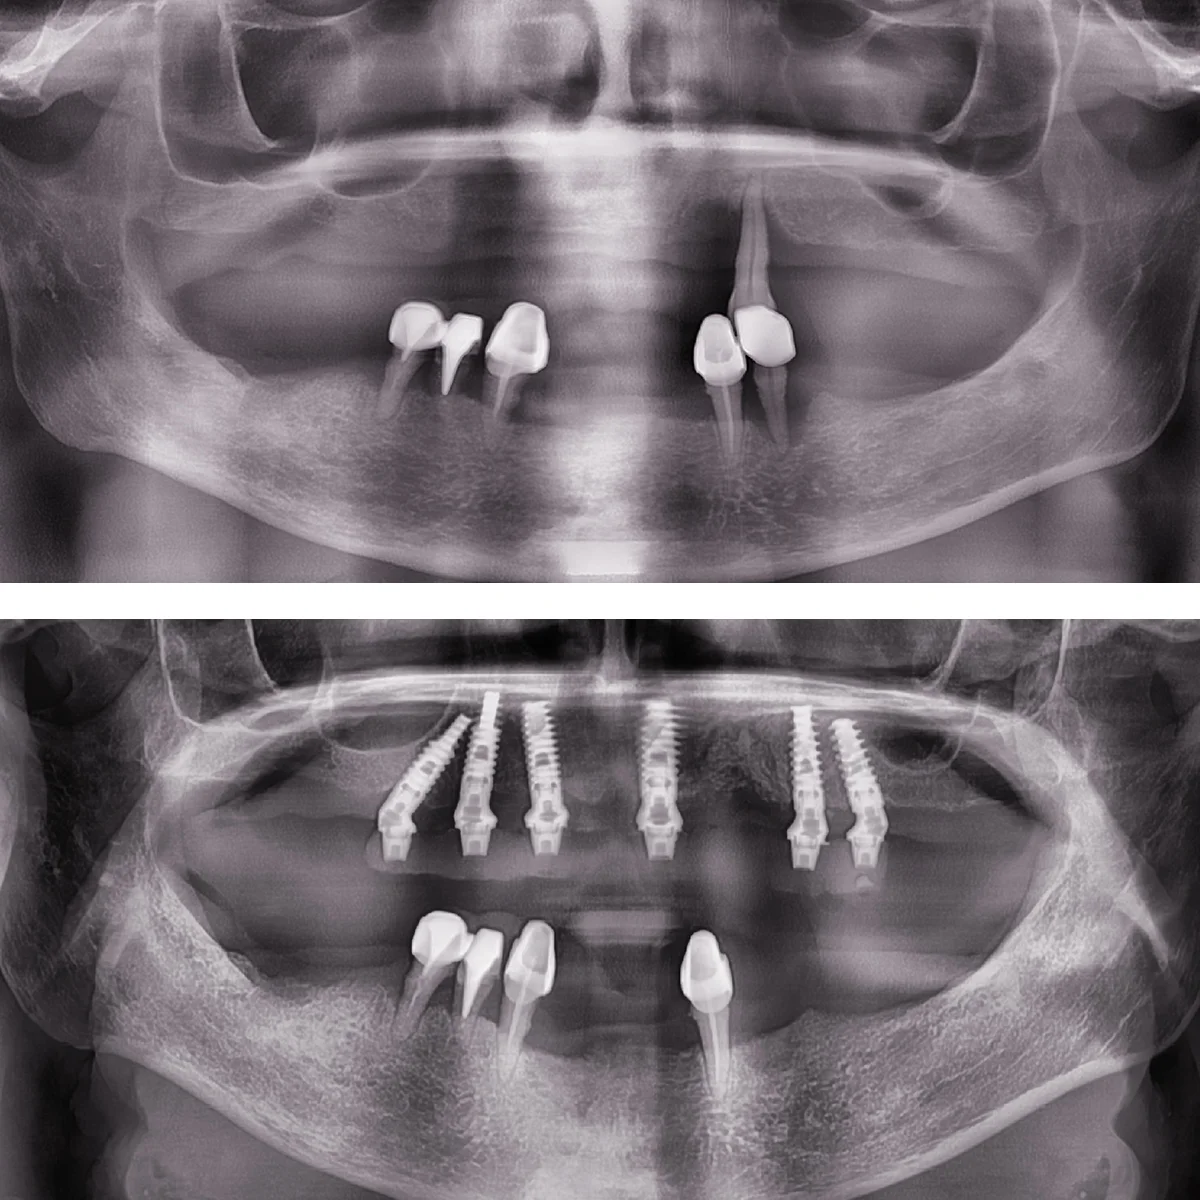

Dinți Ficși în 8-24 de ore pe implanturi dentare cu tehnica All-on-4/All-on-6 este cea mai eficientă și rapidă metodă de restaurare totală a danturii.

Intervenția chirurgicală explicată

Care sunt etapele până la efectuarea intervenției de dinți ficși

- Intervenția chirurgicală